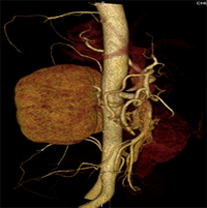

目前臨床對于16層CT的認可主要集中在三維成像領域上的突破.在16層CT的產品平臺上,常規(guī)掃描就能實現(xiàn)滿足三維成像的要求,因此16層也被稱為三維CT,三維成像給臨床診斷帶來了更精確更豐富的診斷信息,我們以臨床為例:

如上圖所示,相鄰的三張軸位圖像未見明顯異常,根據(jù)傳統(tǒng)軸位圖像很難得到準確的臨床診斷。

同一病人利用容積數(shù)據(jù)進行三維處理后,高品質MPR和三維圖像上則清晰顯示了縱向排列的腹腔干與腸系膜上動脈相鄰近,血管發(fā)生變 異,近端血管閉塞,為臨床提供了精確的診斷信息。

從上面的例子可以看到,能否為臨床提供高品質的三維影像成為了16層CT的核心價值,而東芝新一代的 全景三維16層CT擁有最為  先進的3項核心技術,在16層核心價值上的表現(xiàn)自然值得期待。